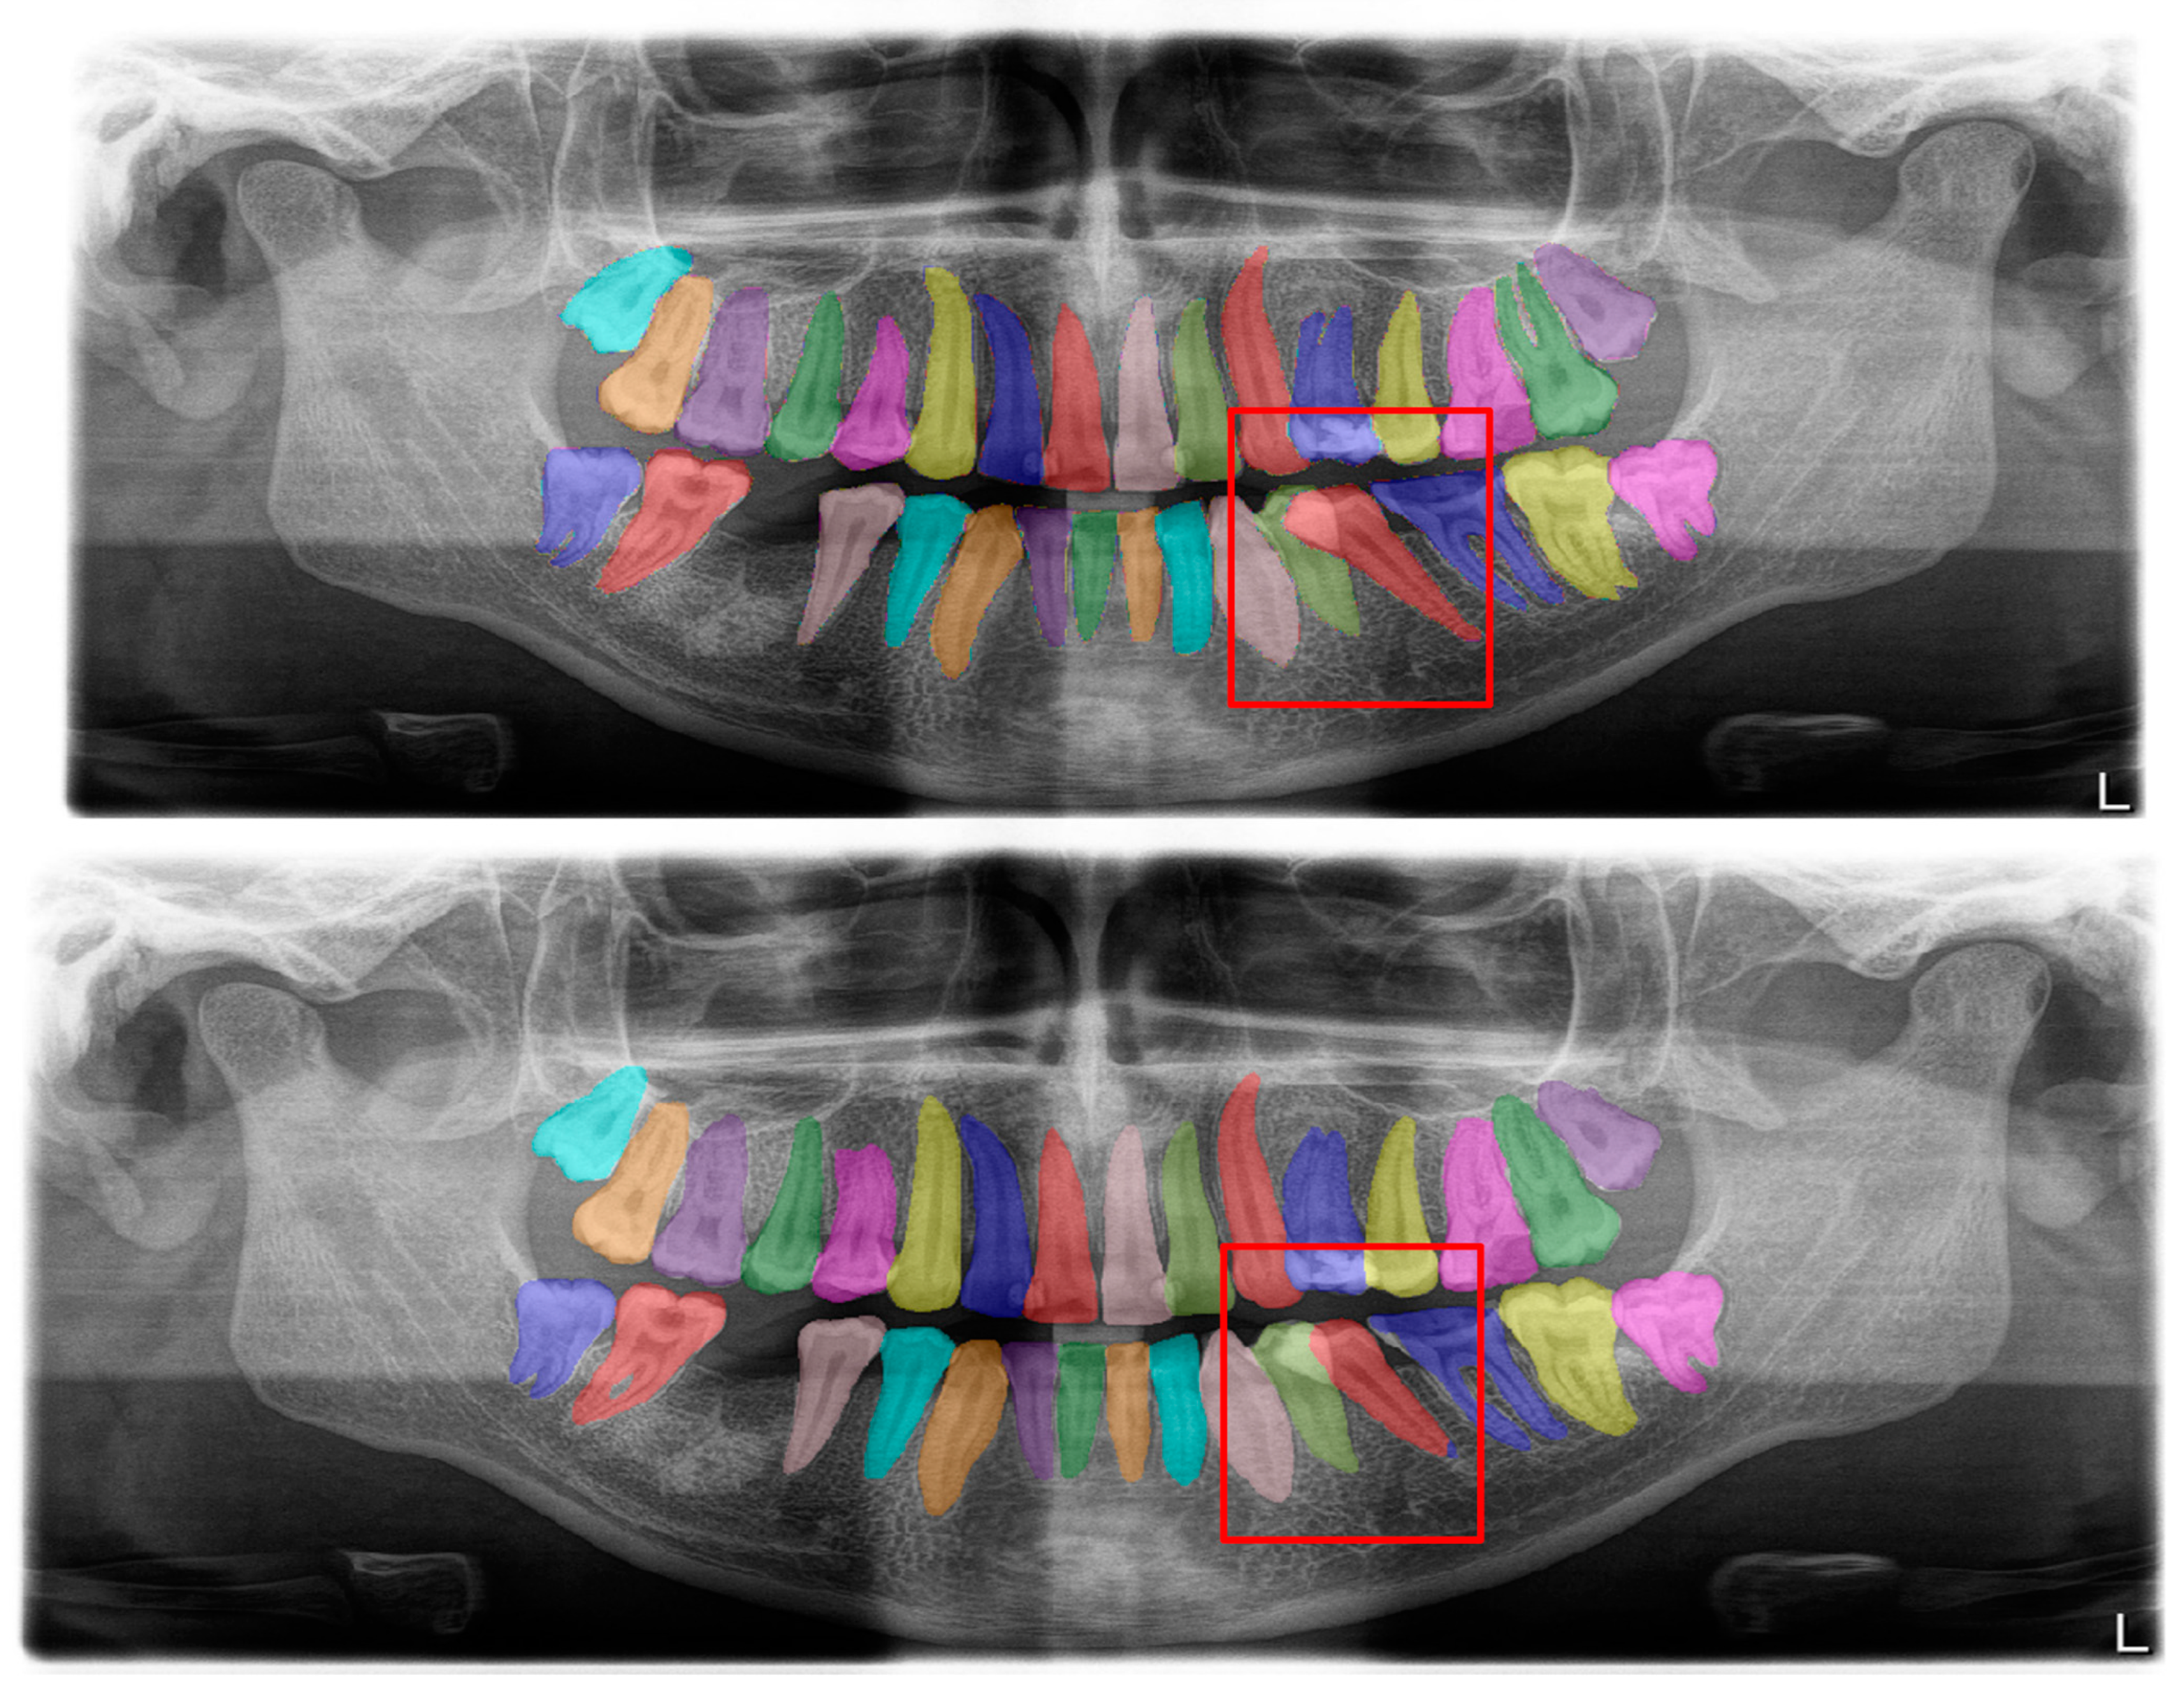

| Structure | DSC |

|---|---|

| Tooth segmentation (Figure 2) | 0.95 |